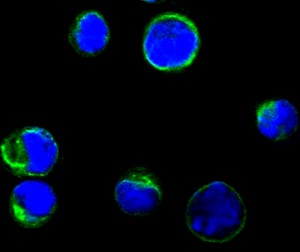

分类: 科研抗体货号: 20352别名: RPS27应用: IF反应种属: Human

-